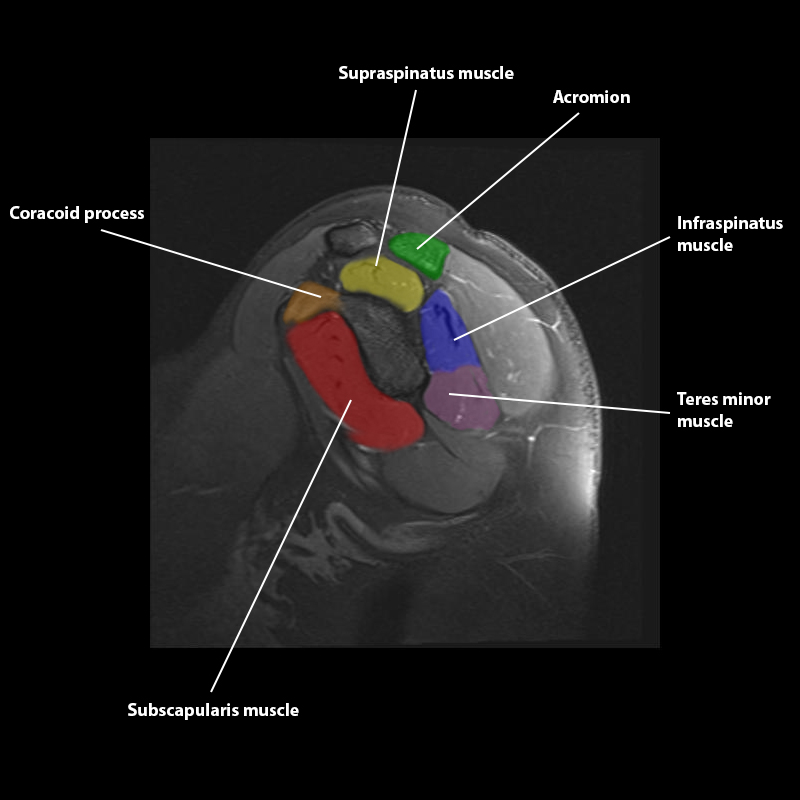

Shoulder MRI Anatomy